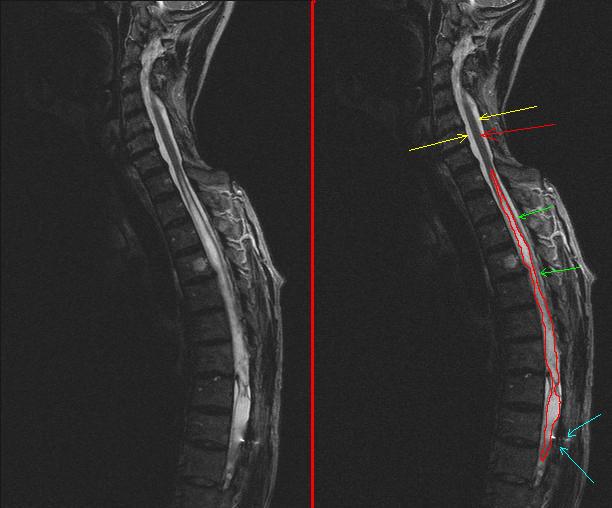

Сирингомиелия что

Сирингомиелия что 111 фотографий